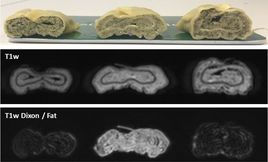

Erste Patienten am Unity MR System untersucht

Am 19.6.2018 wurden in Tübingen die ersten Patienten am Unity System mit dem 1.5 T MRT untersucht und die ersten MR-basierten Bestrahlungspläne berechnet. Die ersten Untersuchungen erfolgten bei Patienten mit Prostata- und Darmkrebs. Die ersten Behandlungen mit dem MR-geführten Linac werden nach der intensiven Schulungsphase erfolgen.

Erste MR-Bildgebung am ersten 1,5 T MR-Linac in Tübingen

Yesterday, when the CE mark for the Unity was announced, the team at Radiation Oncology University of Tübingen has taken the first images. The installation in Tübingen is the first commercially available Unity system in the world. The program of MR-guided Radiation Oncology is funded by the German Research Council (DFG), the Medical Faculty and the University Hospital Tübingen. The team in Tübingen will start to image the first patients today and expect the first treatments within the next few weeks.

Seit der Behandlung des ersten Patienten am 20.09.2018 haben wir bis heute über 100 Bestrahlungen am 1,5 T MR-Linac Unity erfolgreich durchgeführt. Mit der Unterstützung durch Elekta und Philips konnten wir einen reibungslosen Ablauf der Echtzeit-MR-geführten Bestrahlung im täglichen Einsatz entwickeln. Bisher haben wir Patienten mit Metastasen im Beckenraum und in der Brustwand sowie Patienten mit Rektum- und Prostatakrebs behandelt. Bei allen Patienten war der Tumor und die angrenzenden gesunden Gewebe mit der hohen Auflösung der MRT am Bestrahlungsgerät sehr gut sichtbar.

Zusätzlich untersuchen wir mit speziellen MRT-Techniken das Therapieansprechen des Tumorgewebes, um in Zukunft die Therapie entsprechend anzupassen. Eine Übersicht über die Studienprotokolle am neuen MR-Linac finden Sie unter unserer Rubrik "Klinische Studien".